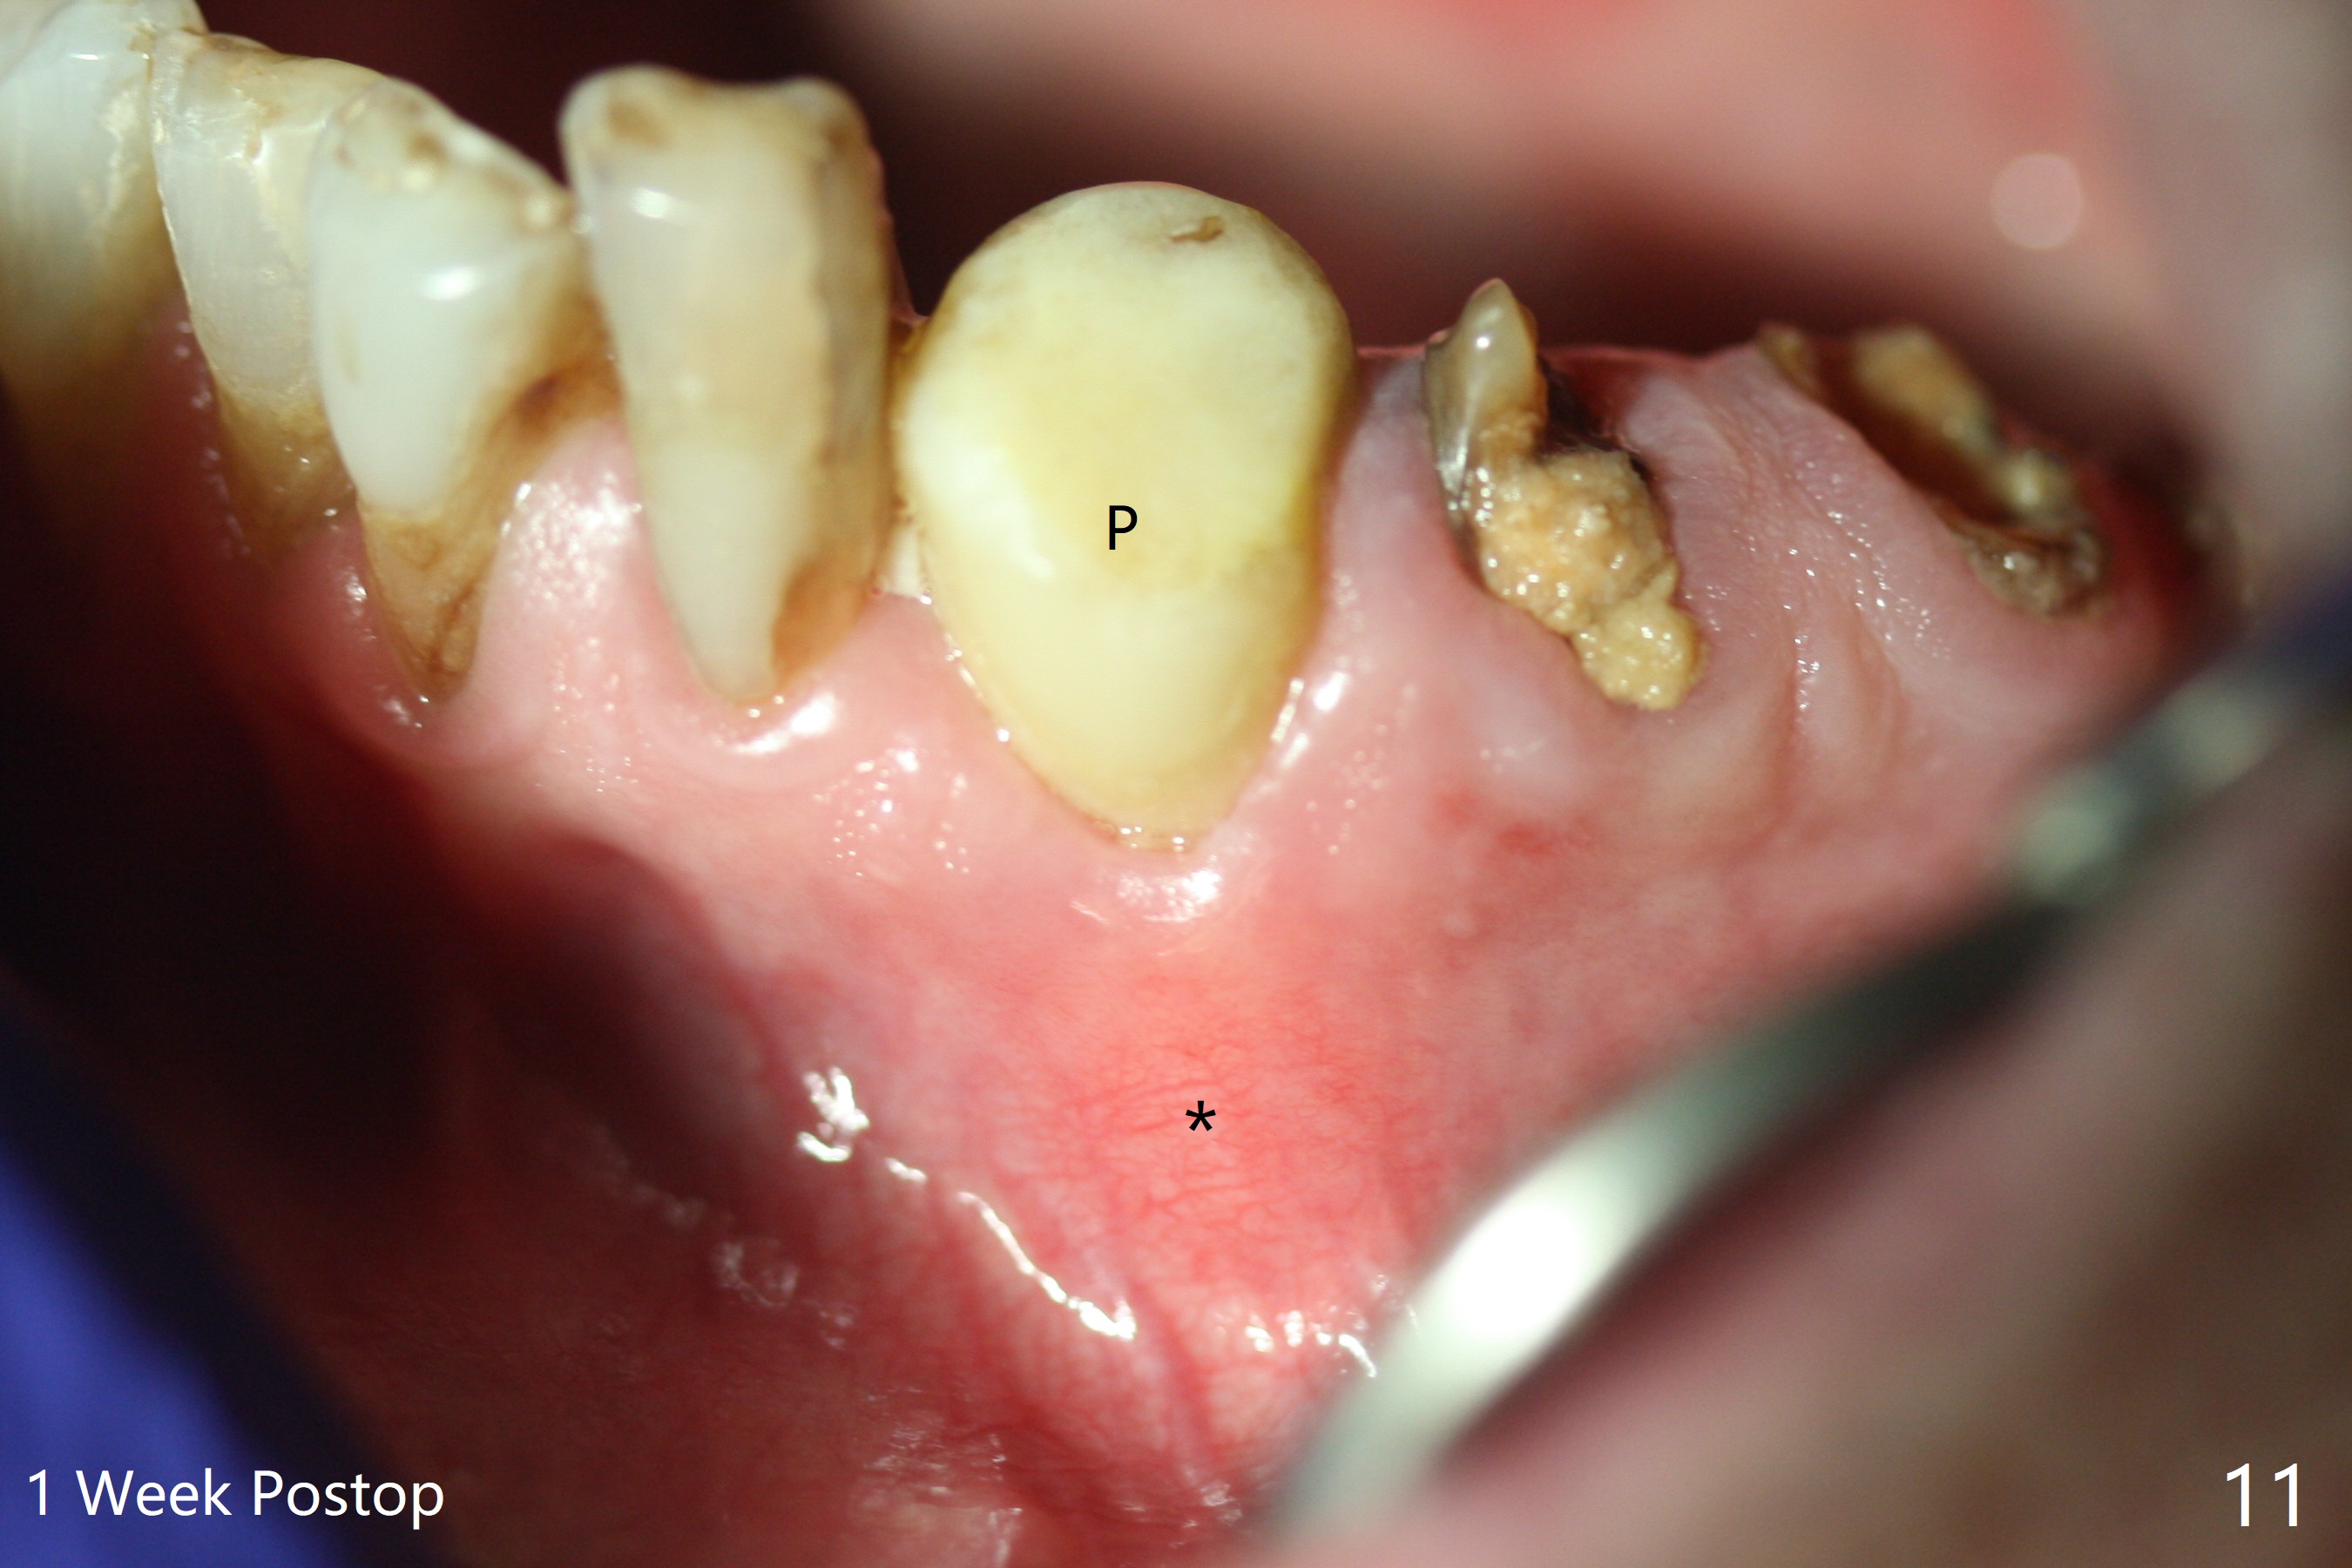

After removal of the split residual roots at #22 (Fig.1), the buccal wall is found to be defective, while the coronal portion of the lingual one (Fig.2 L) is confirmed to be more buccal than the apical portion. A vertical slot is made in the coronal portion of the lingual plate (Fig.3 *) in order to establish osteotomy lingual (Fig.4 O). The depth of the osteotomy in the apical native bone is 4.8 mm (Fig.5 CT coronal section). After the final drill (3 mm) is removed, a 3.8x16 mm implant is placed lingually for secure 2-pointed fixation (Fig.6,7, coronally: mesiolinguodistal; apically: in the native bone (Fig.9)). The essence of the lingual placement is the presence of a large buccal gap for Osteogen plug (Fig.8 yellow) and allograft (Fig.8 red, 9,10 (*)) for potential regeneration of the buccal plate. With bone graft and the overlying provisional (Fig.11 P), the buccal plate seems to have been established (*) 1 week postop. There is no obvious implant thread exposure 8 months postop (Fig.12). But the buccal plate is atrophic when the crown is cemented (~10 months postop, Fig.13).